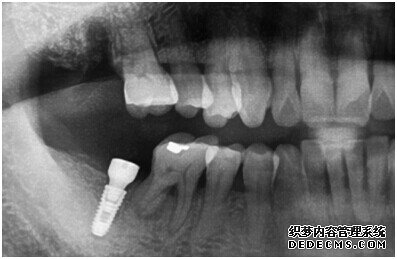

牙齿拍片初步检查

刘女士牙齿拍片初步检查

由CT片检查来看,刘女士口腔健康环境还是很好的,牙槽骨也适合种植牙的条件,而且由我们最后一颗牙是非常重要的,经过专家的建议和详细解释了原因之后,刘女士选择了美国百康种植牙。

种植体成功植入后的CT效果图